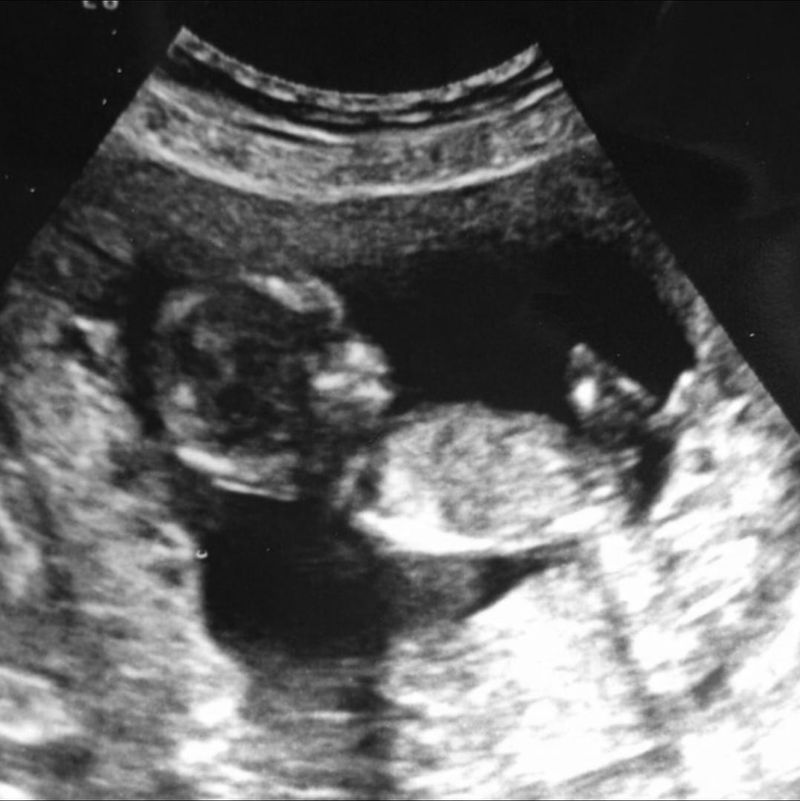

Toen ik op controle moest bij mijn verloskundige, vroeg ze of ik wilde weten wat het geslacht was. We hadden al drie jongens. Omdat mijn man er niet bij was, zei ik dat ze wel mocht kijken, maar dat ze geslacht in een envelop mocht stoppen. Als we het wilden weten, dan zouden we samen kijken. Ik hield mijn ogen dicht en het bleef heel lang stil. Toen ik toch even keek, zag ik geen baby bewegen, maar een baby voorover hangen. Een heel vreemd beeld, wat ik nooit meer vergeet. De verloskundige vertelde mij dat het niet goed was, maar ik hoorde en zag niets meer. Ik wilde naar huis, naar mijn man.

Mijn man schrok zich natuurlijk helemaal rot en voelde zich ook schuldig dat hij mij alleen heeft laten gaan. Hij week geen moment meer van mijn zijde. Diezelfde dag moesten we ons melden in het ziekenhuis en kregen we nog een echo. We hoorden dat het kindje waarschijnlijk al twee weken dood in mijn buik zat. Ik vermoedde dat het kindje gestorven was op het moment dat ik mij beter ging voelen.